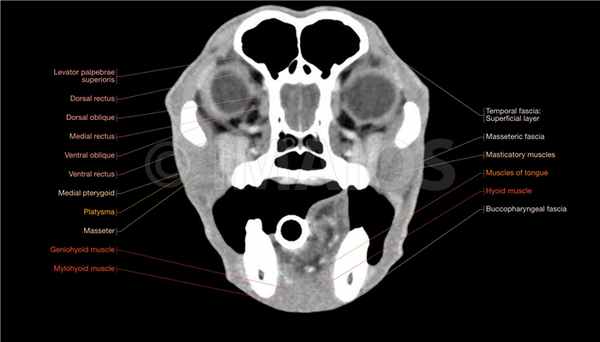

Анатомия головы и черепа собаки в КТ-срезах (кости черепа, мозг, мышцы лицевой части, гортань, глотка, синус лицевой части черепа)

В этом модуле атласа анатомии животных представлены КТ-изображения головы пятилетнего лабрадора в поперечной, сагиттальной и дорсальной (фронтальной) плоскостях, а также 3D-реконструкция костей и кожи. Исследования проводились доктором Сюзанной АЕБ Бороффка (англ. Dr. Susanne AEB Boroffka, PhD), дипломированным специалистом ECVDI (Утрехт, Нидерланды).

Анатомические структуры (740 элементов) с названиями сгруппированы в разделы: